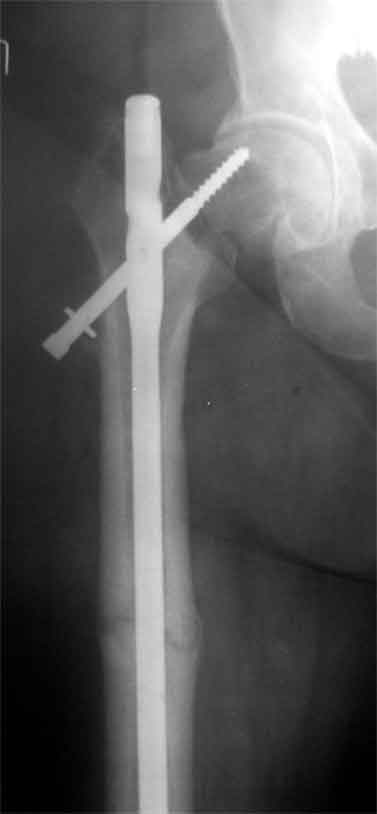

Доброго время суток, коллеги. Обратилась на консультацию пациентка 52 лет. травма и первичный остеосинтез перелома бедра около года назад, далее был обнаружен перелом шейки бедра (возможно ятрогенный), реостеосинтез реконструкционным гвоздем 8 месяцев назад. Конченость не опорна. В больнице, где выполнялись эти вмешательства предложили выполнить THR с длинной ножкой. Возможно ли в такой ситуации добиться сращения шейки при помощи каких-либо остеотомий?

На мой взгляд дистальный перелом срощен, а состояние тазобедренного сустава и молодой возраст пациентки позволяют произвести вальгизирующую остеотомию проксимального бедра. В случае, если нет сращения дистального перелома можно фиксировать длинным DHS; Если есть сращение- обычным DHS.

Применение одного импланта для лечения ипсилатеральных переломов резко ограничено из-за риска осложнениий, связанных с применением неадекватной фиксации. По литературным данным, осложнения после применения зарекламированных реконструктивных гвоздей для лечения ипсилатеральных переломов доходили до 56%.

Несостоятельность фиксации шейки не давала возможности срастись перелому, потому что запланированнная динамическая нагрузка в большинстве случаев прекращалалась из-за вторичного варусного смещения шейки.

В идеале свежие ипсилатеральные переломы надо лечит отдельно каждый:

шейку паралельними шурупами, бедро ретроградным методом. При латеральных переломах шейки 130 градусный DHS с ретроградным гвоздем.

Тогда импланты, не мешая друг другу, создадут компрессию на бедре и скольжение в шейке.

В данном случае навряд ли можно ожидать образования сращения на бедре и еще имеется укорочение засчет варуса.

Для предоперационной планировки необходимо сравнительные ренгенограммы с другой стороны, которая точно укажет истинную длину конечности. КТ

поможет установит сращение на шейке и бедре. Восстановление длины можно сделать за счет вальгусной остеотомии оригинальным методом Blade Plate. На бедро шт ифт ретроградно или пластина, кому что нравится. На мой взгляд, еще имеется шанс спасти головку остеотомией.